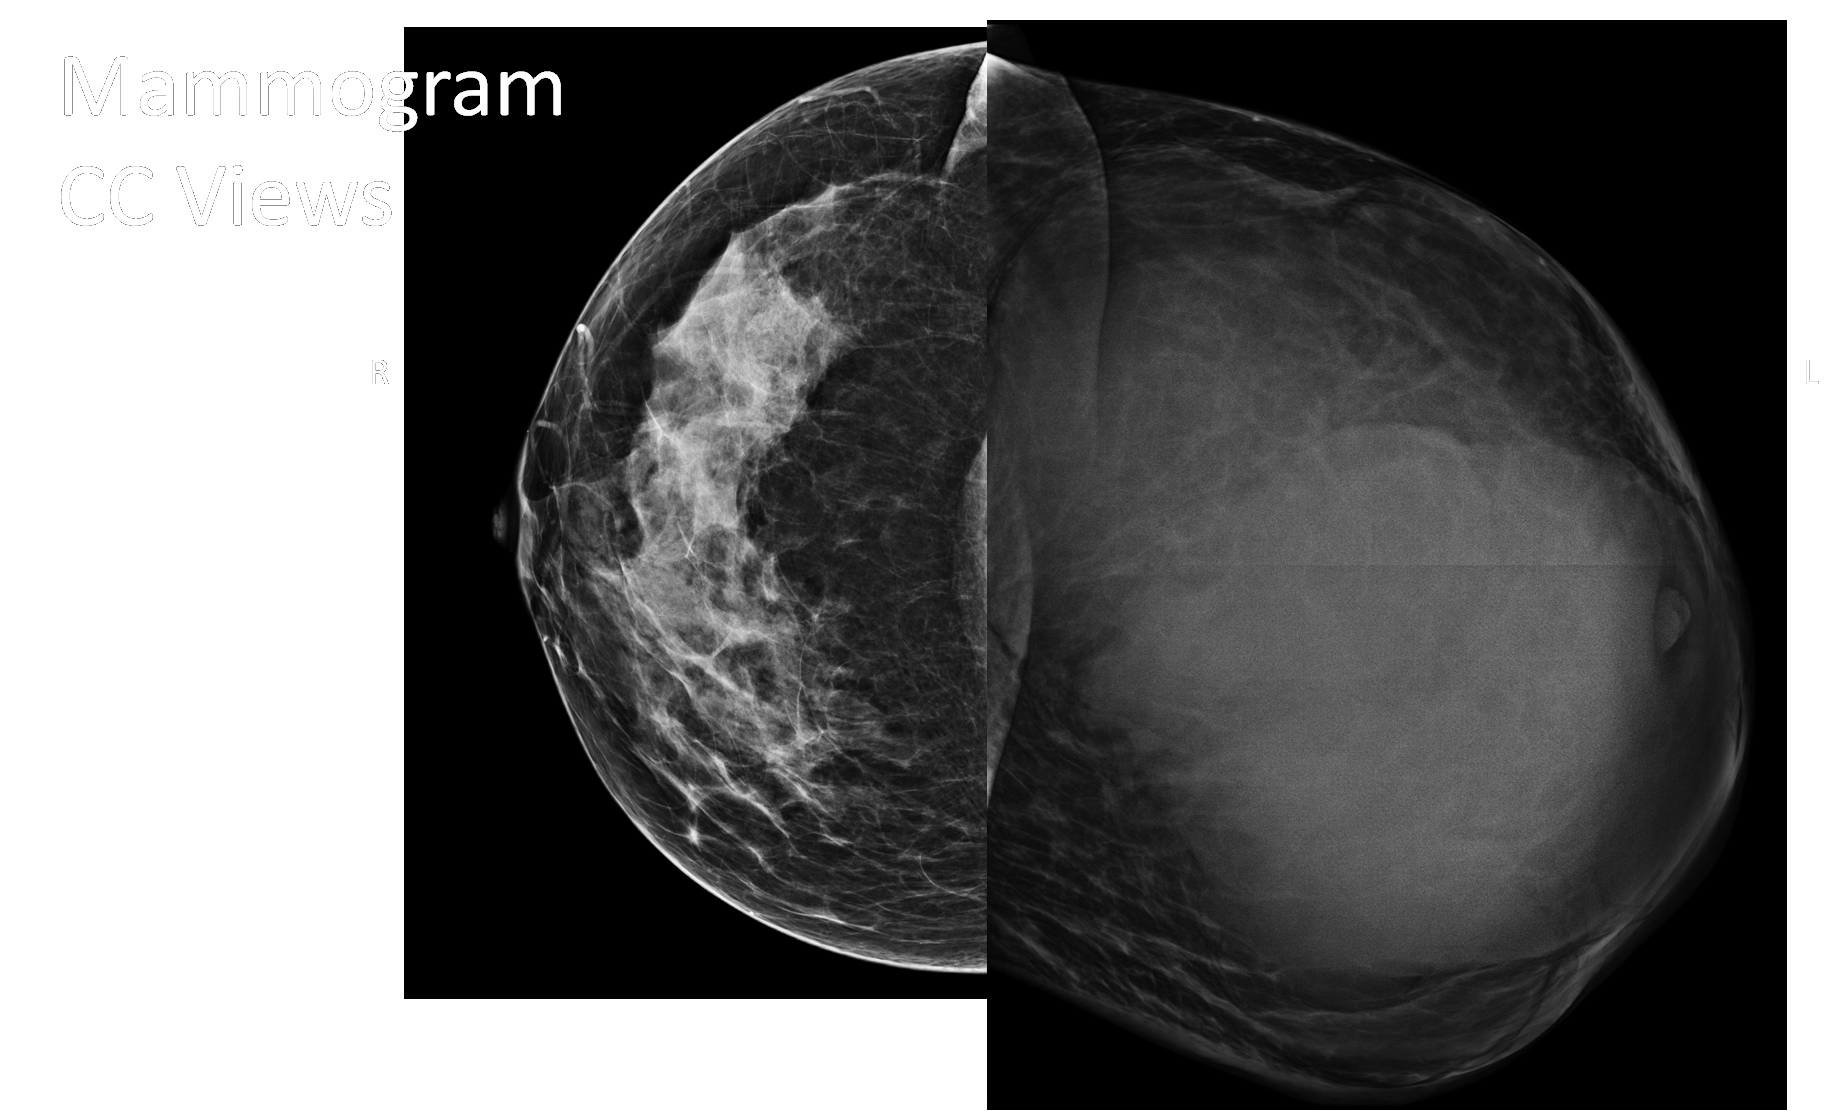

January 2023

40-year-old lady came for a routine mammogram. Previous history of a l...

Read More